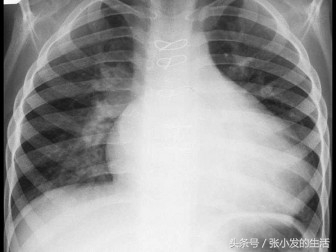

A.原发性(特发性)中枢性尿崩症

B.颅咽管瘤致多饮、多尿

C.家族性尿崩症

D.肾性尿崩症

E.糖尿病性多饮、多尿

正确答案:ABC